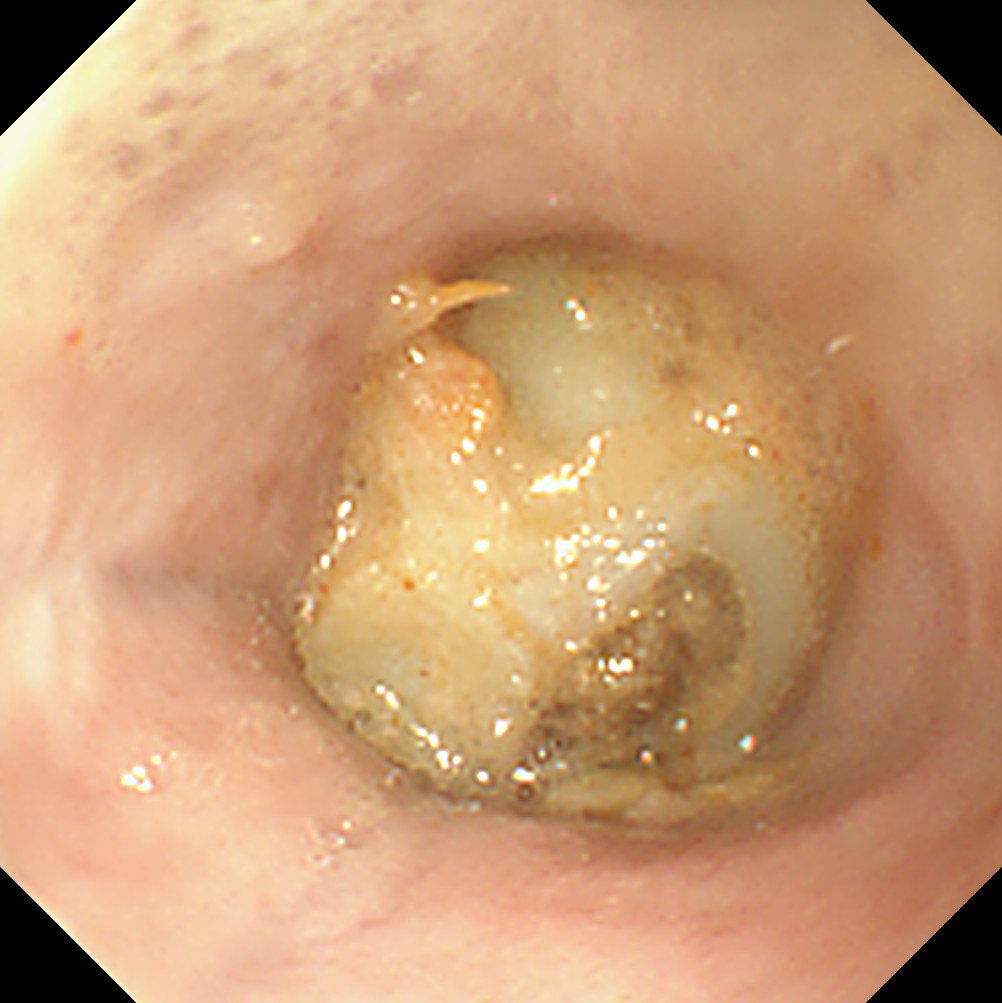

Gastric FBs

As long as grasping instruments are large enough, all except the largest and/or smoothest gastric FBs can be removed endoscopically. However, sometimes it can be frustrating chasing an object around the stomach or dropping it as one tries to pull it through the lower oesophageal sphincter. It is sensible to set a time limit on attempts at endoscopic removal of gastric FBs before opting for surgery, as a simple gastrotomy is often quicker! FBs with an edge or prominence are easier to catch with grasping forceps, whereas basket forceps or a Roth net is better for smooth/round objects.

The biggest frustration with the endoscopic removal of gastric FBs is that the FB often falls out of the antrum and down to the cardia. This occurs when the patient is in the standard left lateral recumbency position as the stomach is insufflated (Figure 5). Having to retroflex the endoscope to grab the FB can then be difficult. Turning the patient into right lateral recumbency will roll the FB down to where it can be retrieved more easily.